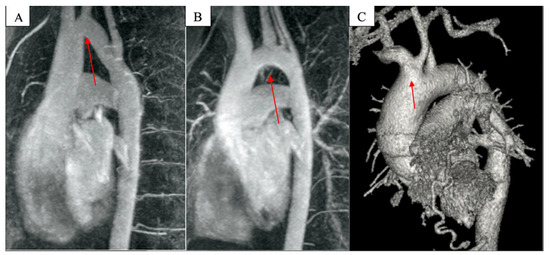

- Based on the geometry in the left anterior oblique position: Gothic, crenel, and Romanesque aortic arches.